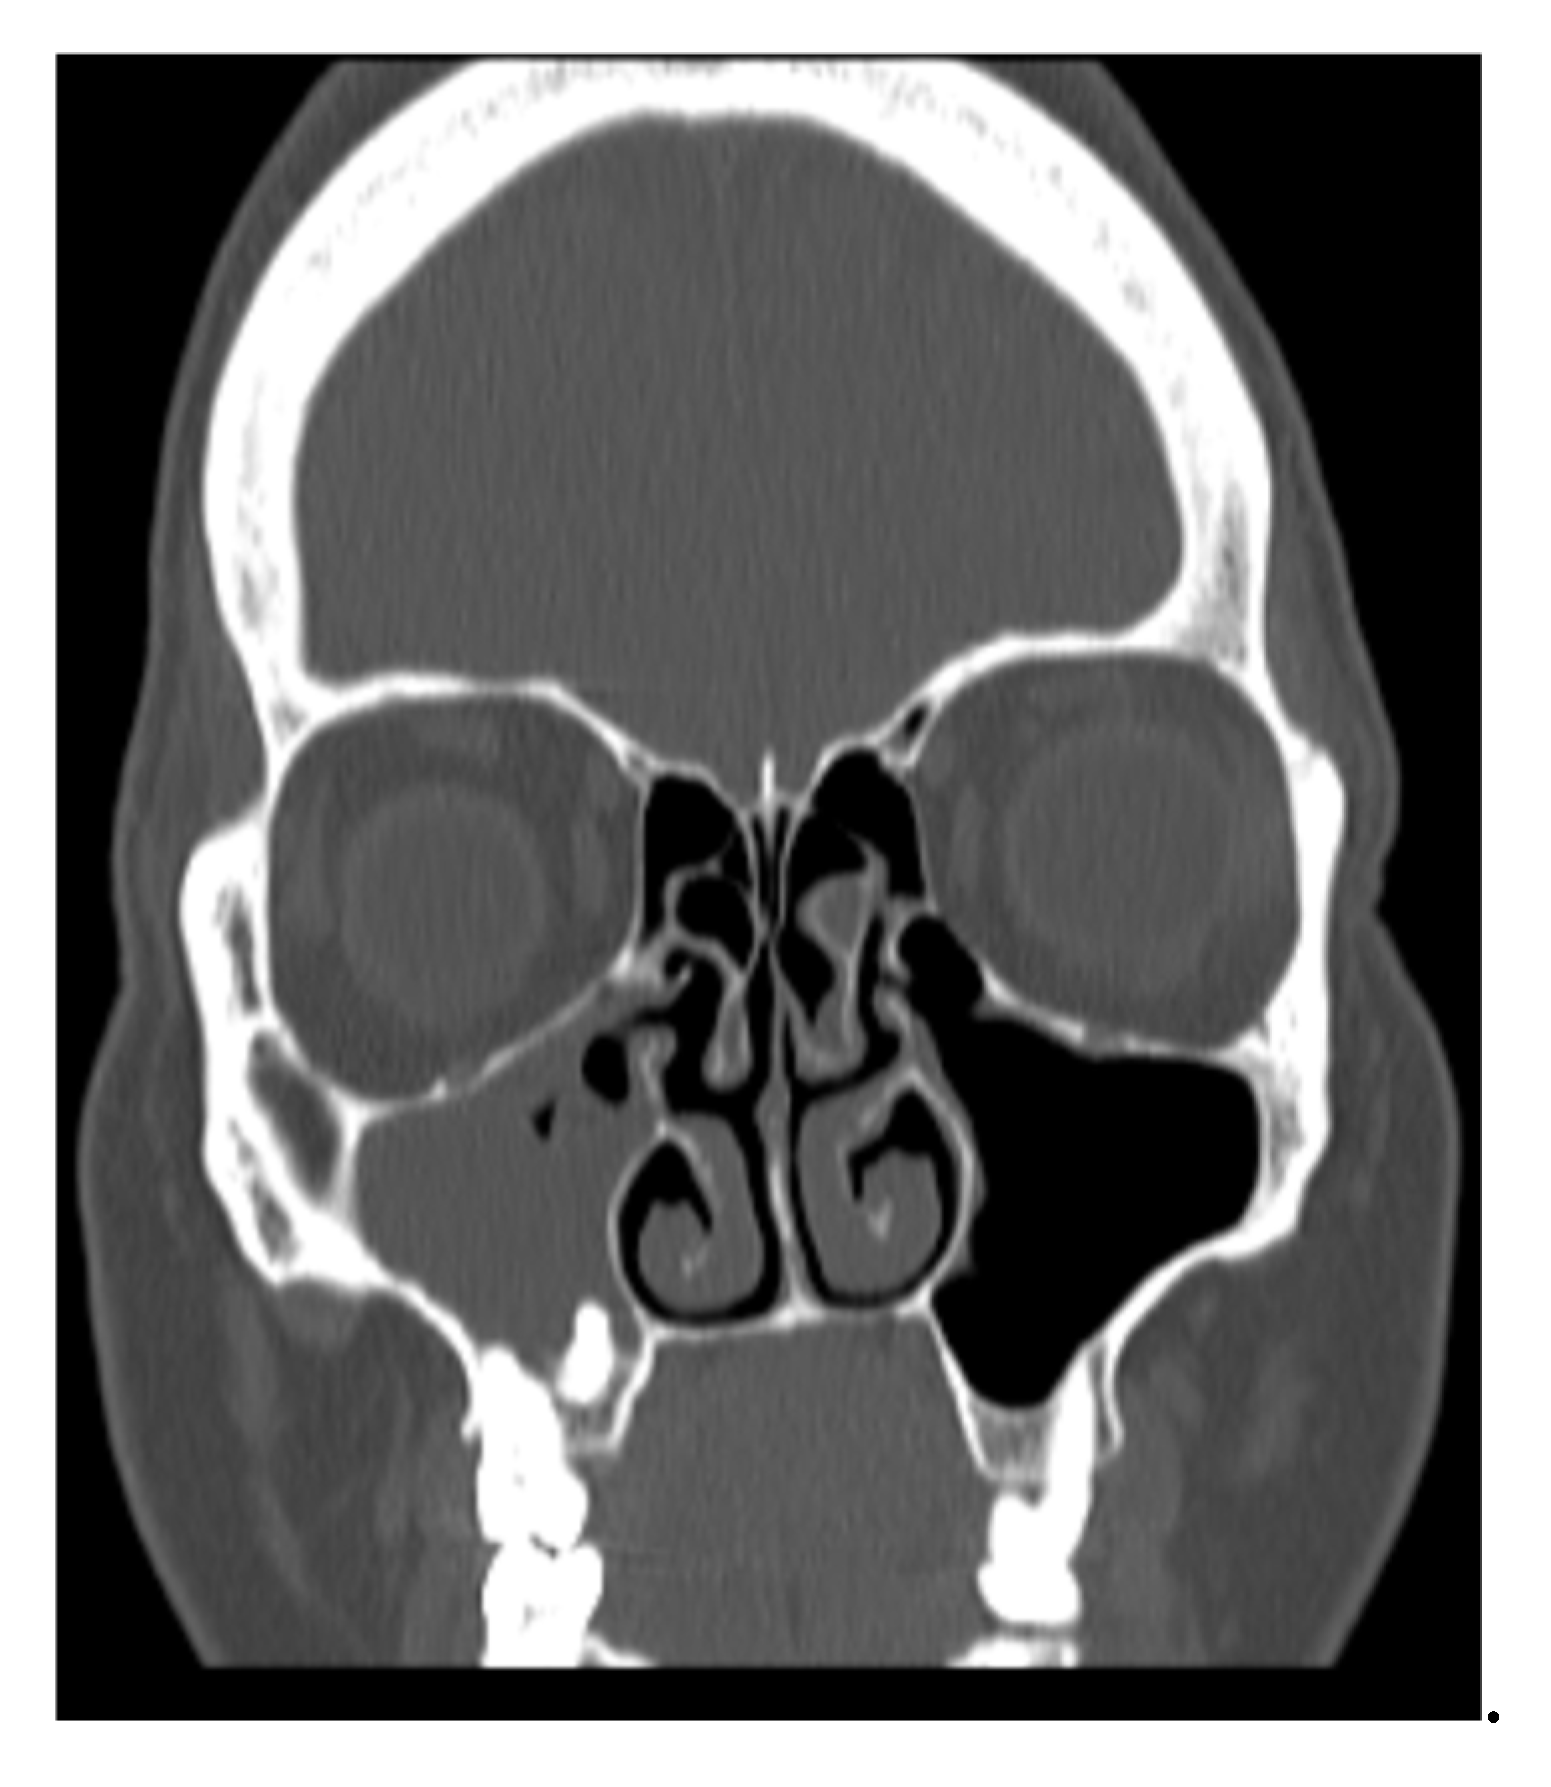

• A patient suffering from sinusitis due to a complication of implantological treatment for at least 4 months, with OAF, without obstruction of ostiomeatal complex and without foreign body can be identified as: TcEaB0O0F1 [Figure 1] [Figure 2]

Figure 1. Slice TC 1 of patient with TcEaB0O0F1.

Figure 2. Slice TC 2 of patient with TcEaB0O0F1.